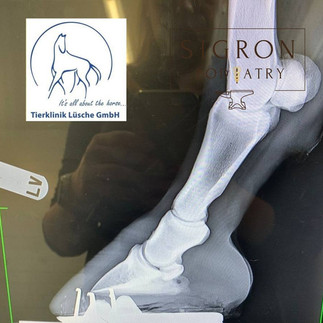

Lameness can side line a horse and its rider for months or even years. When traditional treatments fall short, finding a solution that truly supports recovery becomes critical. Thanks to Farrier Ronald Aalders for sharing how he helped a horse overcome serious mechanical failure and return to soundness with Glushu glue on horse shoes.

"“This particular horse had not been ridden for a long time due to persistent lameness. The owner faced ongoing frustration as the horse’s condition resisted standard approaches. Mechanical failure in the hoof structure created a complex problem that demanded more than routine trimming or shoeing.

I have used Glushu for many years now for complicated cases and I knew that this would be a good solution for this horse.